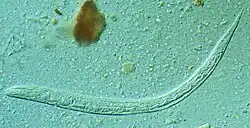

L'anguillule parasite de l'intestin est une minuscule femelle parthénogénétique strongyloïde, très mince et longue de 2 à 3 mm. D'autres formes adultes, mâles et femelles stercoraux (qui concernent les excréments) existent seulement à l'état libre ; elles sont rhabditoïdes et atteignent 1 mm pour la femelle, un peu moins pour le mâle.

L'association avec l'ankylostomose rend fréquemment le diagnostic délicat. Il est très difficile de distinguer les larves d'ankylostome des larves strongyloïdes. Toute diarrhée au long cours, évoluant par crises successives, avec éosinophilie commandera la confirmation parasitologique par examens de laboratoire. Le diagnostic repose sur l'identification au microscope des larves (rhabditoïdes et parfois strongyloïdes) dans les selles (examen parasitologique des selles) ou dans le liquide duodénal. L'examen des prélèvements est nécessaire, mais pas toujours suffisant, parce que l'examen direct des selles est relativement peu sensible et nécessite d'être répété sur plusieurs examens. Le délai de positivité de ces examens après contamination peut atteindre un mois[2].